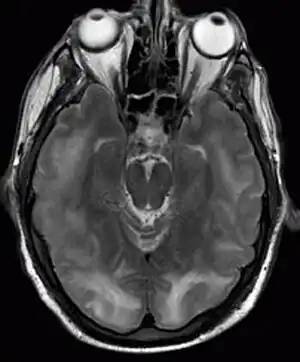

Posterior reversible encephalopathy syndrome visible on magnetic resonance imaging as multiple cortico-subcortical areas of T2-weighted hyperintense (white) signal involving the occipital and parietal lobes bilaterally and pons.

The diagnosis is typically made with magnetic resonance imaging of the brain. The findings most characteristic for PRES are symmetrical hyperintensities on T2-weighed imaging in the parietal and occipital lobes; this pattern is present in more than half of all cases.[1][2] FLAIR sequences can be better at showing these abnormalities.[3] Some specific other rare patterns have been described: the superior frontal sulcus (SFS) watershed pattern, a watershed pattern involving the entire hemisphere (holohemispheric), and a central pattern with vasogenic oedema in the deep white matter, basal ganglia, thalami, brainstem and pons.[1][2] These distinct patterns do not generally correlate with the nature of the symptoms or their severity, although severe edema may suggest a poorer prognosis.[1] If the appearances are not typical, other causes for the symptoms and the imaging abnormalities need to considered before PRES can be diagnosed conclusively.[3] In many cases there is evidence of constriction of the blood vessels (if angiography is performed), suggesting a possible overlap with reversible cerebral vasoconstriction syndrome (RCVS). Diffusion MRI may be used to identify areas of cytotoxic edema caused by poor blood flow (ischemia) but it is not clear if this prognostically relevant.[1][3] Abnormal apparent diffusion coefficient is seen in about 20% of cases.[3]